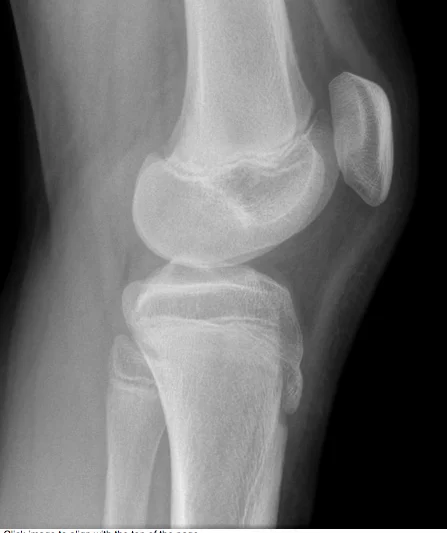

Patient â 40âyearâold female

Mechanism â Jumped from the 2nd floor

Presentation â Pain and swelling around the right knee

Site â Lateral tibial plateau

Type â Simple

Fracture line â Vertical split

Intraâarticular â Yes

Displacements â Small gap in the articular surface

Special issues â Requires surgery for absolute stability